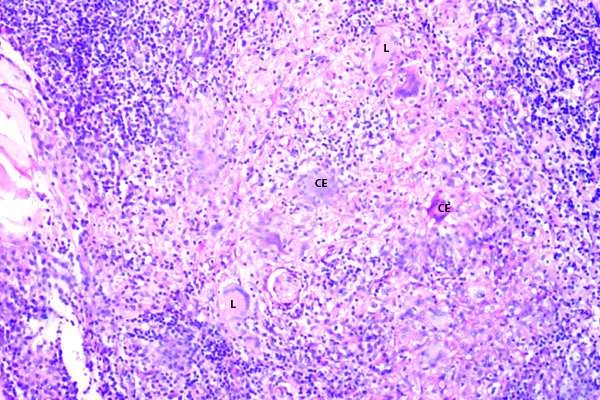

Abundantes células gigantes de tipo Langhans (CL), de tipo cuerpo extraño (CG) y células epitelioides, en el espesor de los granulomas.

Los microabscesos pueden alcanzar las capas más profundas del párpado, disecando las fibras musculares estriadas del orbicular de los párpados (FM).